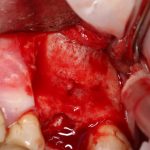

Через 3 месяца — вторая операция — установка имплантата в сформированный объем костной ткани:

Как видите. восстанавливается всё очень легко, никаких дефектов не остаётся, но при этом мы получаем важное преимущество: достаточную свободу движений при формировании субантральной полости и хороший визуальный контроль за состоянием слизистой оболочки. Никакая нажопная оптика или суперпупермикроскоп, к сожалению, не обеспечат подобный контроль при закрытом синуслифтинге. Да, операция получается травматичнее и масштабнее, чем «закрытый» синуслифтинг, но несёт в себе гораздо меньше рисков.